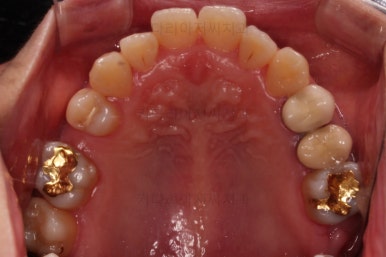

환자분이 선택하신 장치는 데이몬 클리어라고 하는 자가결찰 세라믹 장치입니다.

자가결찰 세라믹 중에 가장 심미적으로 우수한 장치가 데이몬 클리어인데요.

철사를 제외한 모든 파트가 세라믹으로 되어있습니다.

장치를 부착한 모습 참고해 주시고요.

아랫니는 중앙선을 맞추기 위해서 미니스크류를 이용해 한 쪽으로 당기는 중이고요.

윗니 임플란트 할 자리는 적절히 계속 맞춰줍니다.

임플란트 할 공간도 여유롭게 마련이 되었네요.

임플란트 뿌리 부분이 먼저 식립되었고요.